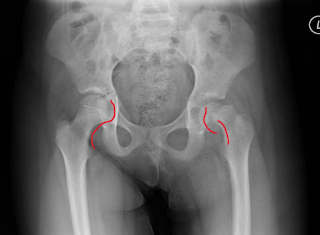

A 13-year-old obese female has had a limp for 3.5 weeks. Her x-ray is shown below.

Image 1. Case courtesy of Dr. Subhan Iqbal and Assoc Prof Frank Gaillard, Radiopaedia.org, rID: 2056